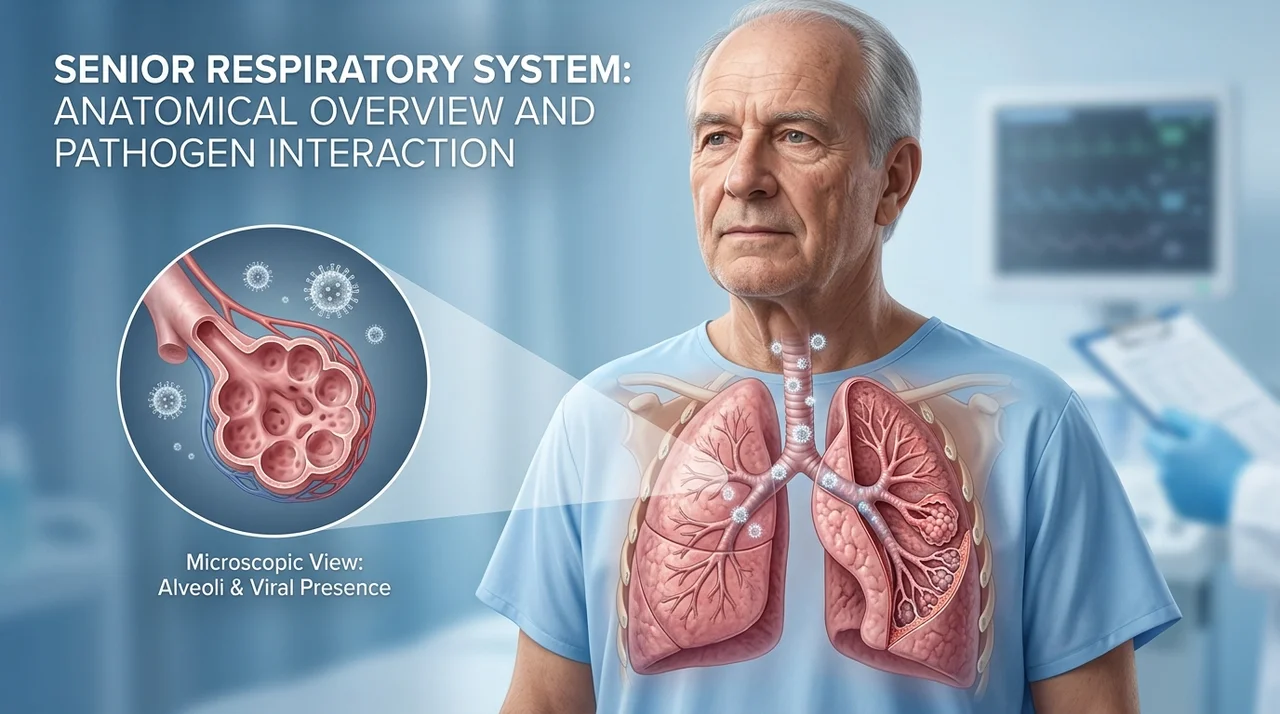

코로나19 바이러스에서 회복된 이후에도 특정 증상이 수주에서 수개월 동안 지속되는 현상을 '롱코비드(Long COVID)' 또는 코로나 후유증이라고 합니다. 이는 단순히 체력이 떨어진 상태를 넘어, 신체 전반의 염증 반응이나 면역 체계의 불균형으로 인해 발생합니다.

코로나 후유증은 특정 장기에만 국한되지 않고 전신에 걸쳐 다양하게 나타납니다. 크게 호흡기, 신경계, 전신 증상으로 나눌 수 있습니다.

- 심한 호흡 곤란: 가만히 있어도 숨이 차거나 입술이 파래지는 청색증이 나타날 때 (폐렴 또는 폐섬유화 가능성)